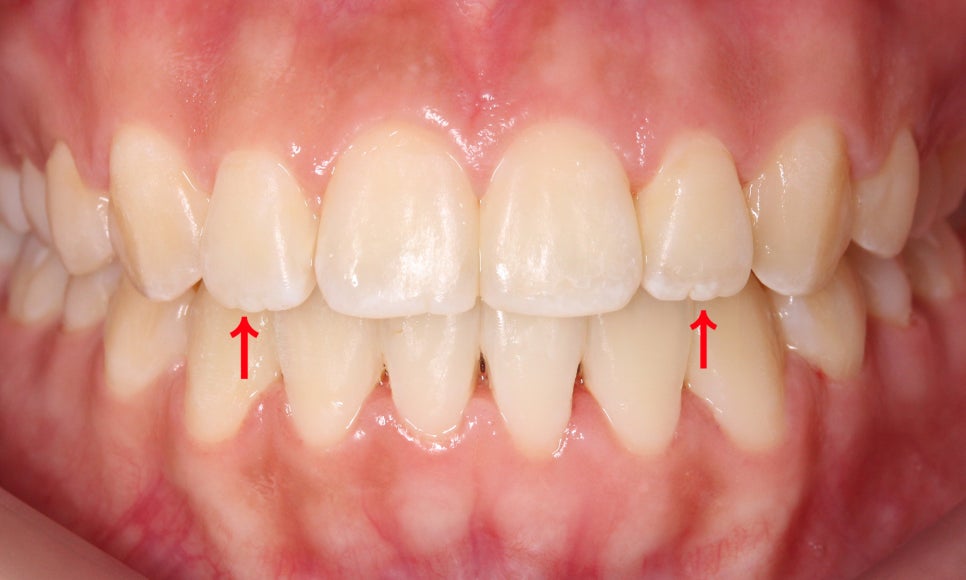

환자분께서도 교정이 끝난 뒤

치아의 끝 모양이 많이 매끄러워진 것을

확인할 수 있습니다~

앞쪽으로 뻐드러져 있던

작은앞니(측절치)도 교정이

마무리 되고 가지런해지면서

톱니같던 끝 모양이

매끈해진 모습인데요!

반대쪽 치아의 경우 아직

마모가 많이 진행되지 않아

마멜론이 미세하게 남아있는 모습입니다.